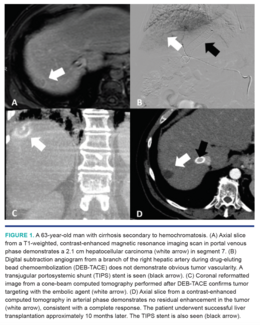

Robert M. Cannon, MD; Majd Habash, BS; Souheil Saddekni, MD; Souheil Saddekni, MD; Andrew J. Gunn, MD

In this article, we will discuss our approach to liver-directed therapies for transplant-eligible and near transplant-eligible patients at the University of Alabama in Birmingham, Alabama.